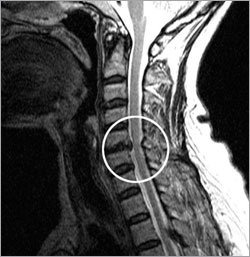

首椎間板ヘルニアは首骨の間の柔らかな原版模様の椎間板が裂けて周辺神経を押すこと。首の後部分の痛症と痺れる感じが、神経に沿って肩と腕につながれば、椎間板ヘルニアを疑ってみなければならない。

最も重要な判定基準は中樞神経を圧迫するかどうかだ。突き出た椎間板が中樞神経をひどく圧迫すれば、寝られないほど苦しい。このような場合は、ちょっと転んだだけでも全身麻痺が起きる恐れがあるので手術が必要だ。

椎間板が中樞神経を押してはいるが、痛症と痺れが弱いかない場合もある。医者によって即時手術しなければならないという方と、物理治療をしながら経過をみてみようという方に意見が分けられる。神経が押された程度と症状、手術の安全性に対して充分に検討して手術するかどうかを決めなければならない。

椎間板が末梢神経だけ押す場合は、大半が薬物治療と物理治療を並行する。しかし、末梢神経だけ押されても、その程度がひどくて腕と手の感覚が鈍くなり、力が抜けるぐらいなら手術を考慮する。